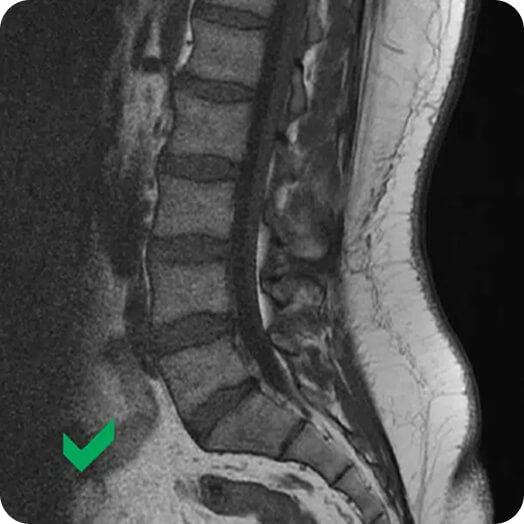

FOTO: Slika magnetne resonance (MRI) - nespecifične bolečine v križu

Pri nespecifičnih bolečinah v križu je struktura primerna in brez posebnosti.

Slika magnetne resonance (MRI), ki prikazuje nespecifične bolečine v križu

Natančna diagnoza o tem, kaj povzroča bolečine v križu, ni mogoča. Rentgenske sike in MRI na strukturi ne pokažejo nepravilnosti, zato je težko ugotoviti, kaj je dejanski vzrok za bolečino.